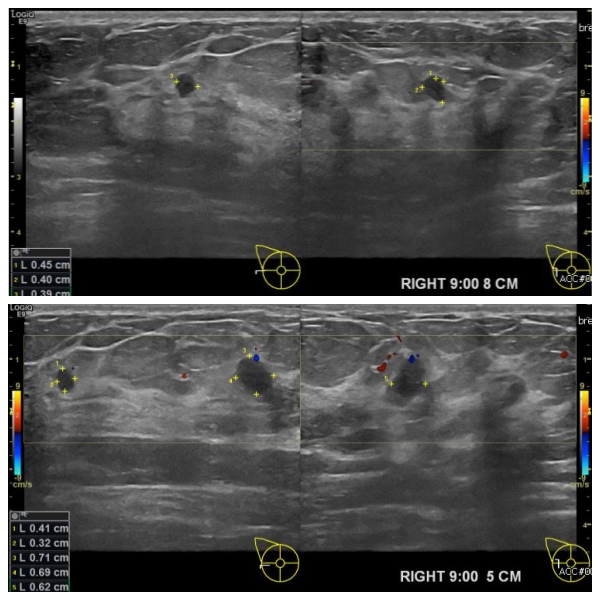

상기환자 우측 유방의 통증으로 내원하시여 본원 경과관찰 하시던 30대 여성분으로

본원 초음파상 우측 9시 방향에서 8cm 과 5cm 떨어진 거리에 새로생긴 멍울 조직검사

시행하여 각각 우측 유관암 진단 되었습니다.